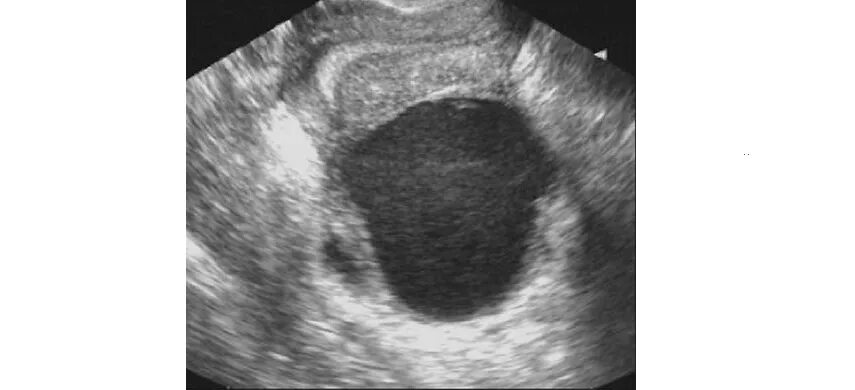

Метастазы в матке